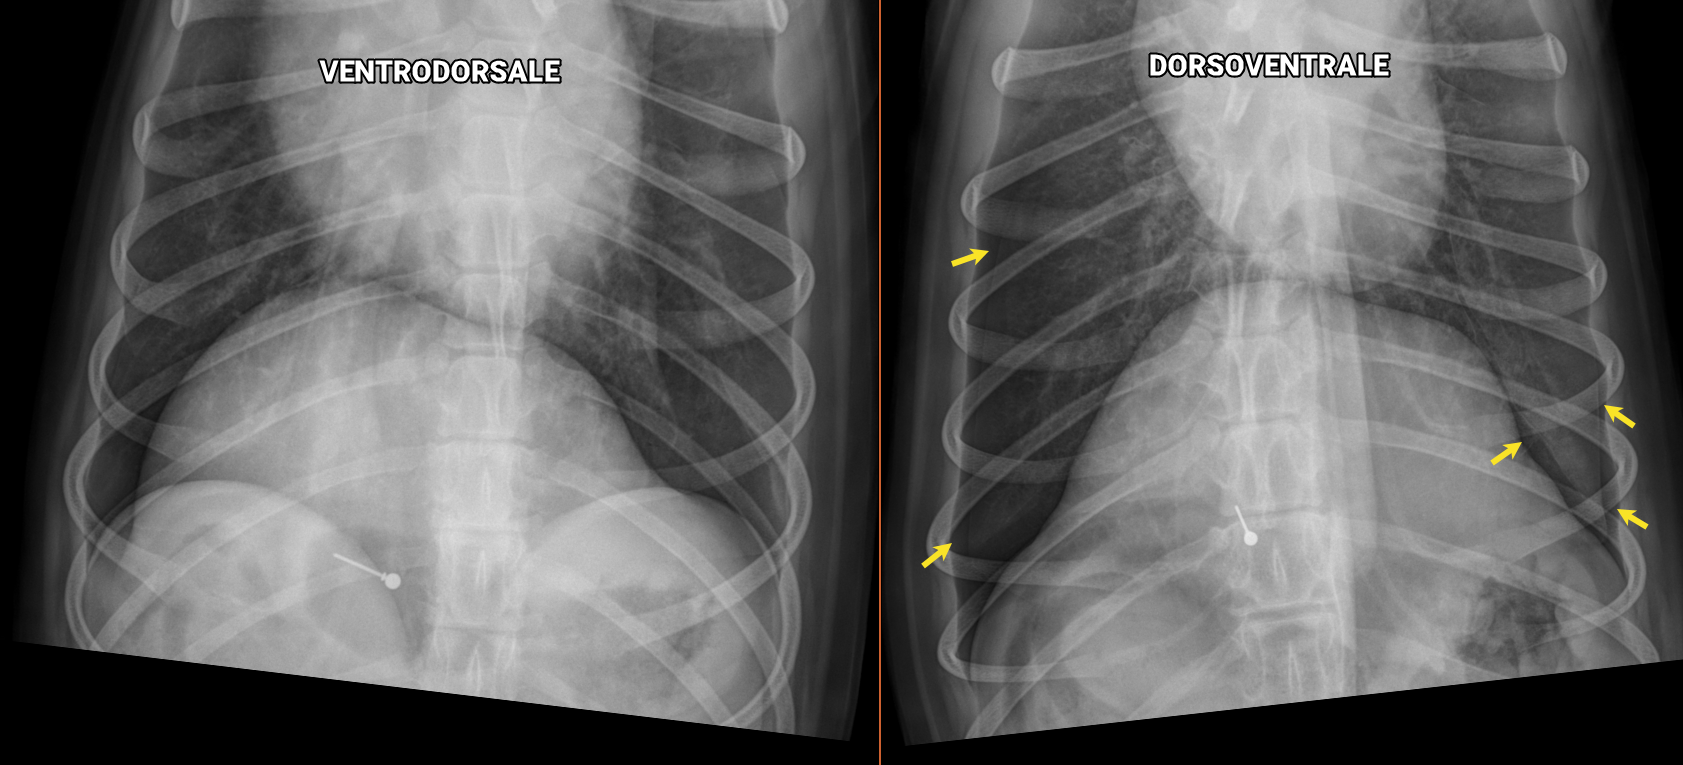

L’examen radiographique standard comprend deux vues latérales en plus d’une vue orthogonale. Plus souvent, la ventrodorsale (VD) est employée pour former le trio. Mais est-ce toujours le meilleur choix ? Explorons différentes situations cliniques qui justifient l’emploi d’une dorsoventrale (DV) plutôt que d’une VD, ou l’inverse.

D’abord, le décubitus dorsal peut empirer la détresse respiratoire d’un animal en dyspnée. La DV prise en décubitus sternal est plus sécuritaire et moins stressante dans ce contexte, pour l’animal… mais aussi pour les manipulateurs !

La ventilation réduite des lobes caudaux provoquée par le décubitus dorsal limite la visualisation de certaines structures caudodorsales étant donné le plus petit volume d’air entourant les tissus mous pulmonaires, notamment les vaisseaux pulmonaires caudaux. Ceux-ci sont en effet plus faciles à évaluer et à mesurer lorsque les poumons sont en pleine expansion, soit en décubitus ventral.

Voici un chat domestique de 7 ans mâle castré présenté pour suivi de sa condition cardiaque. En plus de l’évaluation de la silhouette cardiaque, un examen attentif des vaisseaux pulmonaires crâniaux et caudaux est requis.

En comparant les deux projections, on peut apprécier que la dorsoventrale met davantage en relief les vaisseaux des lobes caudaux (flèches jaunes). On peut aussi y voir que l’extrémité caudale des lobes pulmonaires s’étend plus caudalement en DV (flèches noires), confirmant leur plus grande insufflation.

Ce concept s’applique aussi à la détection de nodule ou de masse pulmonaire caudodorsale. À l’inverse, les structures situées dans les poumons ventraux (incluant le lobe accessoire) sont mieux visibles sur une VD comme ces portions sont alors mieux ventilées.

Ce chien boxer croisé de 12 ans mâle castré avait été présenté pour toux, vomissements et bruits respiratoires augmentés à l’examen. En plus de la pathologie alvéolaire ventrale signalant une bronchopneumonie, un nodule pulmonaire caudo-dorsal était suspecté sur les vues latérales (flèches jaunes), mais n’était pas bien visible sur la VD soumise à ce moment.

Lors du suivi radiographique de la bronchopneumonie, une DV a été effectuée et a permis de confirmer le nodule pulmonaire au lobe caudal droit.

La DV est également idéale pour l’évaluation cardiaque, puisque le cœur bascule moins et sa position dans le thorax est plus constante d’un animal à l’autre, facilitant la détection de changement de forme ou de taille.

La recherche d’effusion pleurale est un autre exemple de l’utilité de la VD. Lorsque l’animal est sur le dos, le liquide se distribue dorsalement entre les lobes pulmonaires, remplissant davantage les scissures interlobaires qui deviennent alors plus évidentes. De plus, ce liquide déplacé dorsalement laisse la silhouette cardiaque mieux dégagée, facilitant son évaluation, comme celle du médiastin crânial.

À l’opposé, le gaz libre dans l’espace pleural fuira la gravité et permettra un diagnostic plus fiable de pneumothorax en décubitus ventral (DV), pour dans l’exemple ci-bas:

Voici une goldendoodle de 5 ans stérilisée présentée pour tachypnée après avoir été frappée par une voiture.

Comparativement à la VD qui ne permet pas de confirmer un pneumothorax chez ce chien, la DV met en évidence une légère accumulation de gaz dans l’espace pleural bilatéral (flèches) associée à une légère rétraction des lobes pulmonaires. En effet, comme le gaz libre s’accumule en portion non déclive des espaces pleuraux, celui-ci devient plus évident en décubitus sternal comme la portion dorsale du thorax est plus large que sa portion ventrale et mieux dégagée des superpositions (avec le coeur et autres steuctures médiastinales).

Pour finir, il est toutefois important de souligner qu’une DV sera techniquement plus difficile à obtenir sans obliquité sur un chien à thorax profond et effilé.